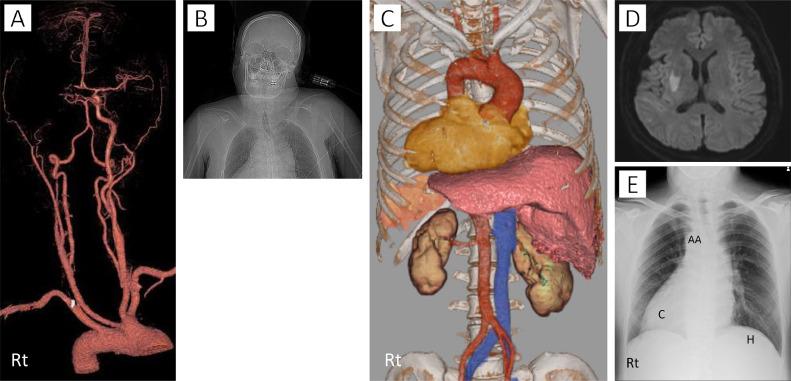

Situs inversus is a rare congenital abnormality characterized by mirror-image transposition of the major visceral organs and vessels. Few reports have discussed the use of mechanical thrombectomy in acute ischemic stroke with situs inversus. We present such a case, to raise awareness and deepen the knowledge on these cases. A 44-year-old man was admitted to our hospital with sudden-onset dysarthria and left-sided paresis. Computed tomography (CT) angiography revealed situs inversus and occlusion in the internal carotid artery. First, intravenous tissue plasminogen activator was administered, followed by immediate reperfusion with mechanical thrombectomy. We achieved thrombolysis in cerebral infarction grade 3. After the procedure, the patient fully recovered. Prompt diagnosis is crucial for rapid recanalization in patients with vascular anomalies such as situs inversus.

内脏反位是一种罕见的先天性异常,其特征为主要内脏器官和血管呈镜像转位。很少有报告讨论过在患有内脏反位的急性缺血性卒中患者中使用机械取栓术。我们报告了这样一例病例,以提高对这些病例的认识并加深了解。一名44岁男性因突发构音障碍和左侧肢体无力入住我院。计算机断层扫描(CT)血管造影显示内脏反位和颈内动脉闭塞。首先,给予静脉注射组织型纤溶酶原激活剂,随后立即进行机械取栓术实现再灌注。我们达到了脑梗死3级溶栓效果。术后,患者完全康复。对于患有诸如内脏反位等血管异常的患者,迅速诊断对于快速再通至关重要。